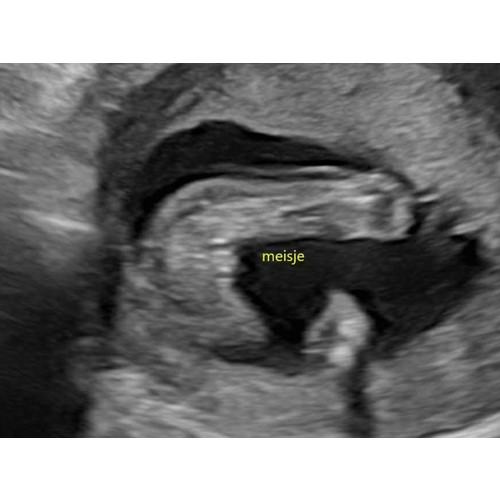

Dit was de echo van ons meisje. (met 17, 1weken)